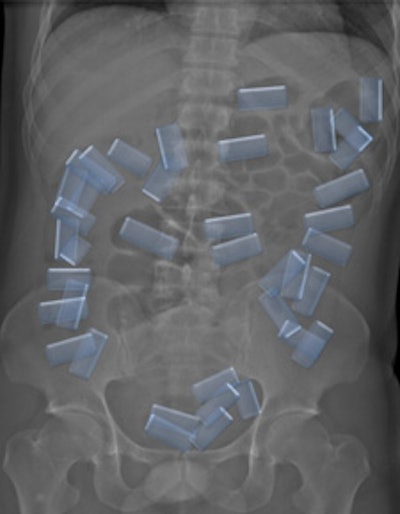

Top left: Low-dose linear slit digital radiography (LSDR) of a typical body packer with 145 intracorporal packs along the alimentary tract. Bottom left: Magnified view of the packs. Note the radiolucent rim within the periphery of the packs due to air trapping creating the so-called "double-condom sign" and "halo sign." Top right: DR of a typical body packer with 83 cocaine packs in the gastrointestinal tract. Bottom right: Note the longitudinal packs (weight approximately 10 to 12 g) projecting over the colon. The magnified view depicts the typical "double-condom sign" due to inevitable air trapped within the wrapping layers during manufacture.DR and low-dose linear slit digital radiography exams were less accurate. CT exams had an overall accuracy rate of 97.1%, followed by DR (71.4%, and 60% for low-dose linear slit digital radiography).